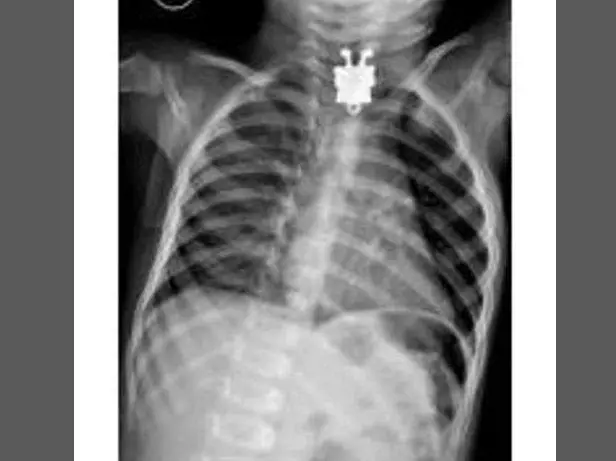

Oggetti bizzarri che hanno trovato la loro strada all'interno del corpo umano, e documentati grazie alle pazze radiografie raccolte dal dottor Frank Gaillard. Quest’ultimo ha fondato Radiopaedia.org, un sito collaborativo che raccoglie casi radiologici e articoli medici a tema.